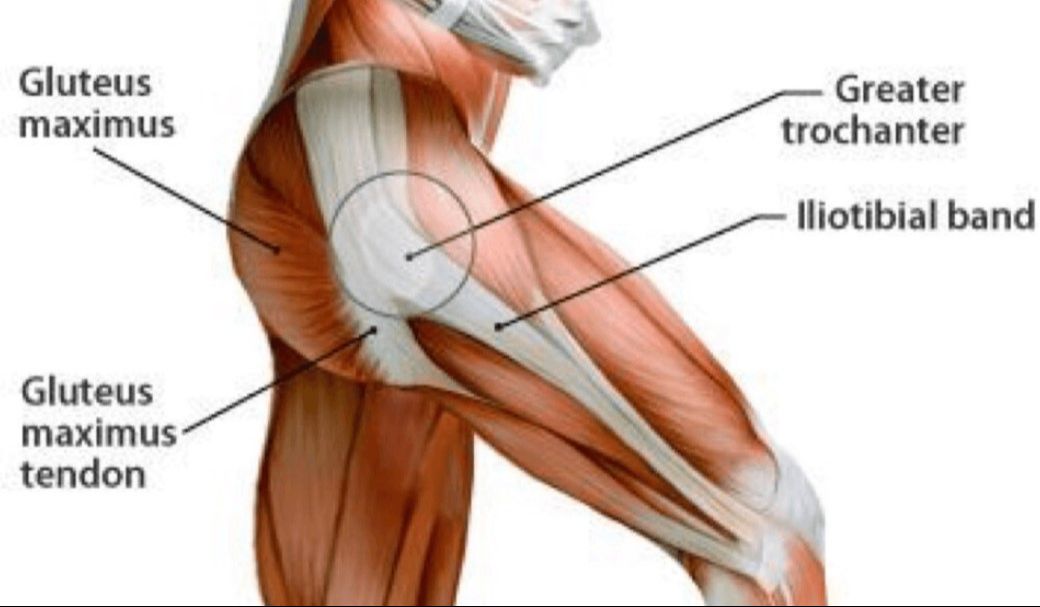

Before we dive into bursitis, let's first get a better understanding of the hip. Bursitis can occur in other area, such as the shoulder, but for today we're focusing on the hip. The principles will apply to all areas of bursitis.

The greater trochanter is a common area of bursitis. As you can see in the diagram, it's a central location for muscles and connective tissue to connect. The Iliotibial band (IT band) is of great importance. You have to consider why the bursitis began in the first place and it usually has to do with the functionality of the surrounding tissues.

As you can see the bursa sack lies between the greater trochanter bone and the gluteus maximus muscle. The IT band runs over the top of this area stabilizing the knees and hips.